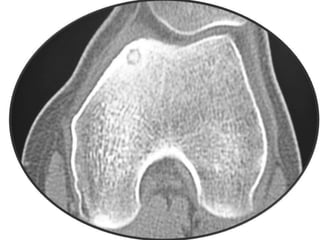

Osteoid Osteoma - CT

• CT is more accurate than MRI.

• CT helped in confirming the diagnosis of

osteoid osteoma in 74% of cases.

• Szendroi et al reported accuracies of about

66% in the diagnosis of intra-articular lesions

and 90% in extra-articular lesions.

• To date, CT scanning is the primary

investigational tool for the definitive diagnosis

of osteoid osteoma.

Osteoid Osteoma -CT • CT is more accurate than MRI. • CT helped in confirming the diagnosis of osteoid osteoma in 74% of cases. • Szendroi et al reported accuracies of about 66% in the diagnosis of intra-articular lesions and 90% in extra-articular lesions. • To date, CT scanning is the primary investigational tool for the definitive diagnosis of osteoid osteoma.